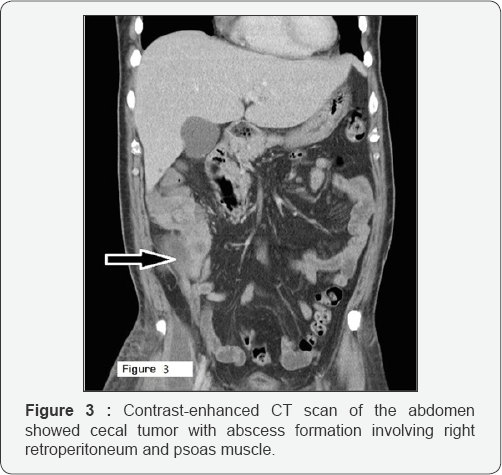

Abdomen was palpated soft with tenderness over the right lower quadrant of abdomen. Laboratory data revealed white blood cell (WBC) count of 8,400/μL, band of 8%, neutrophil of 82%, hemoglobin of 12.4g/dL, platelet count of 36,000/μL, aspartate aminotransferase (AST) of 79 U/L and C-reactive protein (CRP) of 32.25mg/dL. Computed tomography (CT) of right thigh showed scattered, abnormal air accumulation in the subcutaneous layer and muscle layer of right thigh (Figure 2). Further, abdominal contrast-enhanced CT scan showed right colon tumor with abscess formation involving right retro peritoneum and psoas muscle (Figure 3). We applied empiric antibiotic therapy with teicoplanin 200mg and meropenem 500 mg intravenously every 12 hours and fluid resuscitation. Patient received emergent laparotomy and debridement. A 5 cm x 4 cm ulcerative tumor found at cecum and perforated to retroperitoneal space.